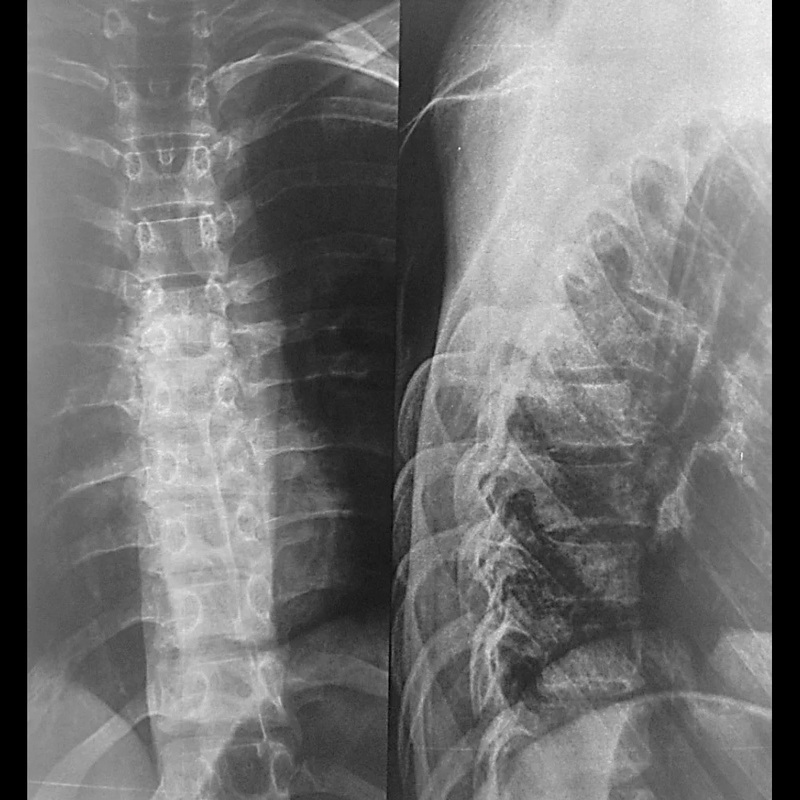

Медицинские снимки: рентген позвоночника сбоку